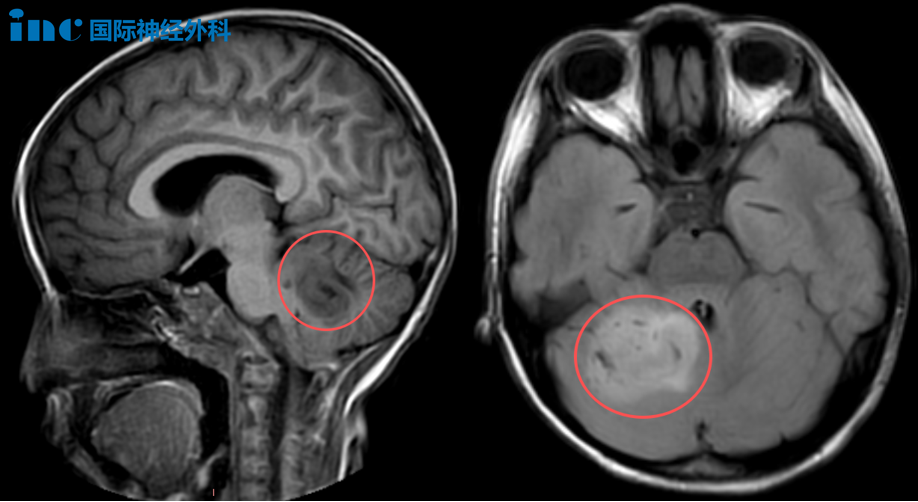

1、6岁女孩小脑占位性病变

一名被诊断为“小脑占位性病变”的女孩乐乐,3天时间,多次呕吐、头晕、恶心,父母心急如焚,最终找到了巴教授。这一次,让他们下定决心手术的,是与巴教授面对面交流时,巴教授笃定的一句:“这个肿瘤可以手术。”